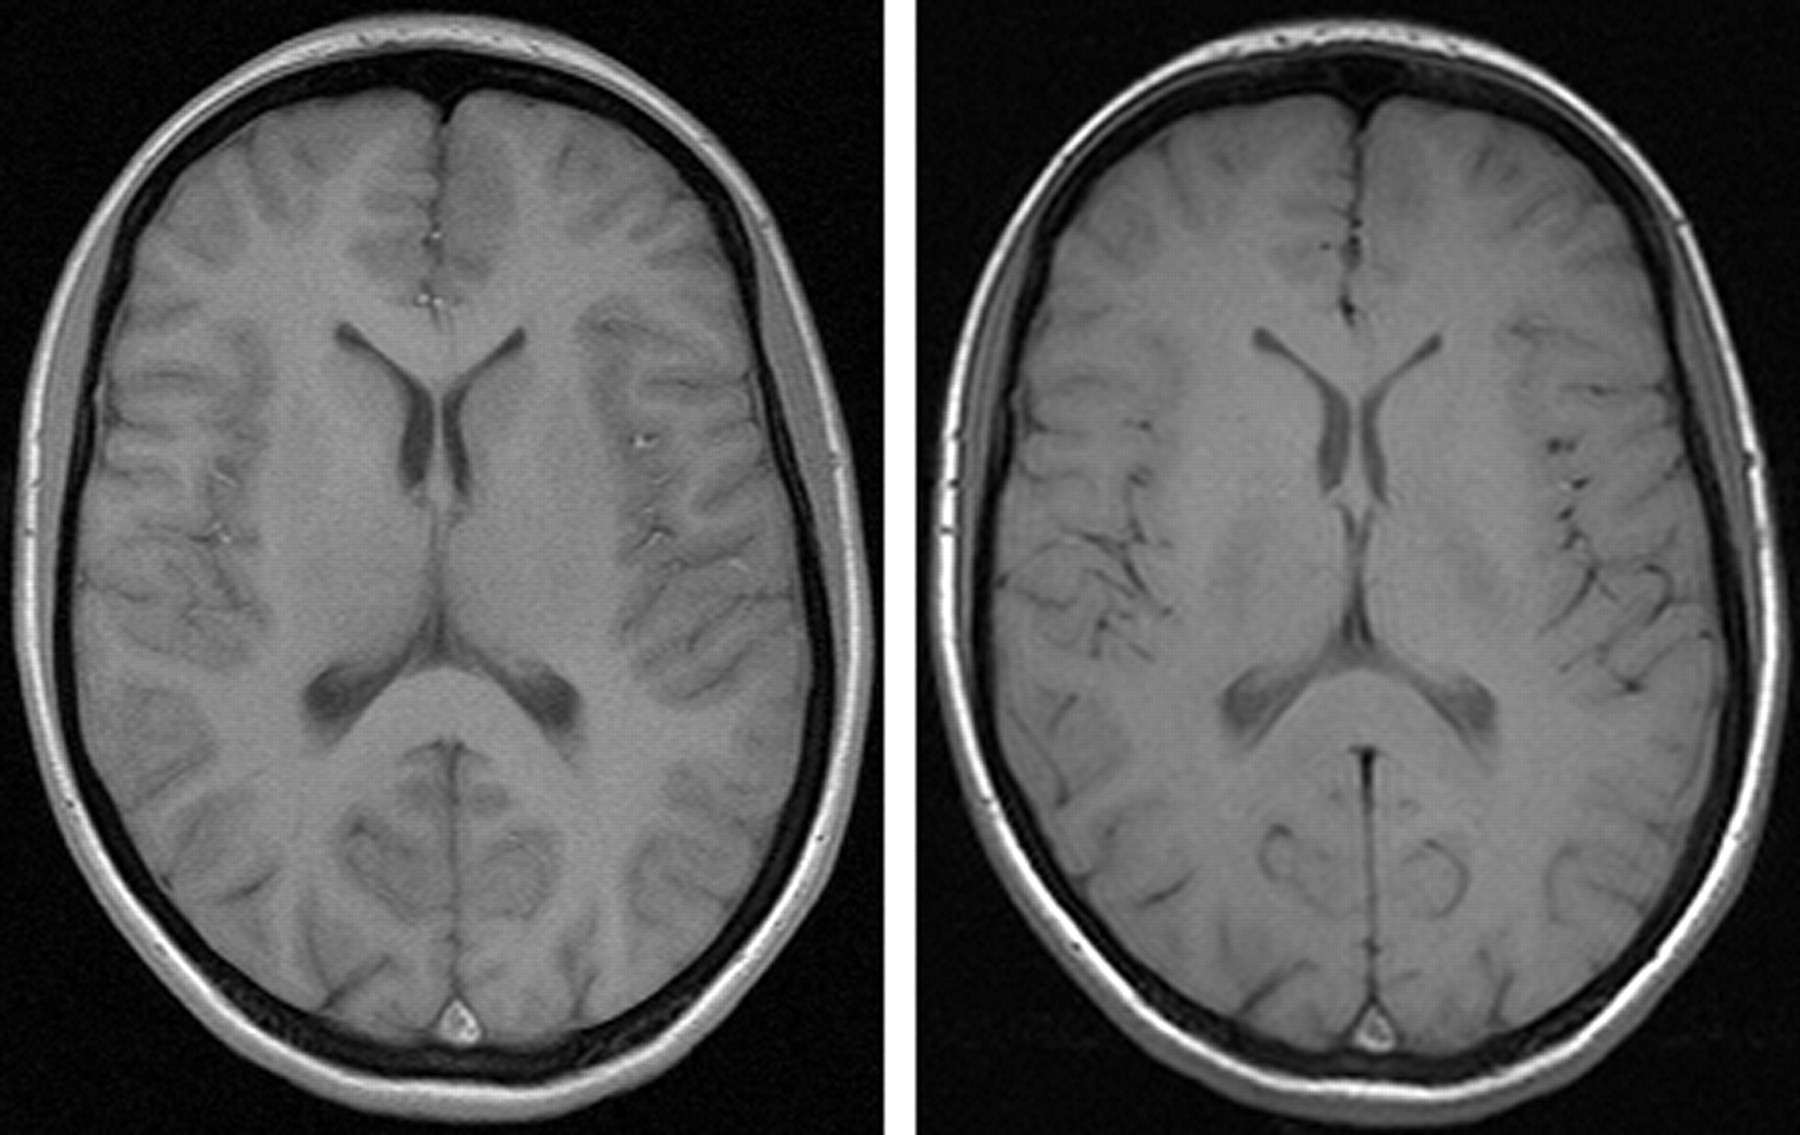

Apparently, gray-to-white matter contrast is reduced in spin-echo T1 imaging at 3T (30) when compared with 1.5T (Fig 6). There are several factors contributing to this observation. T1 times of gray and white matter lengthen and converge at higher fields (31–33). Moreover, shielding effects induced by eddy currents prevent central parts of the image from being properly excited (16), which results in reduced signal intensity of the basal ganglia region. In addition, magnetization transfer effects are enhanced at higher B0, thus reducing signal intensity and contrast. There are several ways to compensate for these effects. For example, inversion recovery sequences appear very well suited if one is only interested in increasing gray to white matter contrast (Fig 7). The inversion pulse, however, interferes with visualization of contrast enhancement following gadolinium administration. Enhancing lesions may not be visible (Fig 8), because in inversion recovery sequences, unlike conventional T1 spin-echo sequences, the tissue with the shortest T1 does not necessarily exhibit the brightest signal intensity, depending on T1. Therefore, inversion recovery sequences are not quite useful for comparative pre- and postcontrast T1 spin-echo imaging, regardless of B0. A different approach to increase gray-to-white matter contrast during T1-weighted spin-echo imaging at both field strengths is to reduce the excitation flip angle (34). Although this reduces SNR slightly, the gain in gray-to-white matter contrast is obvious and more pronounced at 3T (Fig 9). The effect can be predicted from theoretical calculations (35) by using known T1 and T2 relaxation times of gray and white matter (33) but is empirically larger than the theoretical predictions at 3T, probably because of shielding and magnetization transfer effects (34).

Left, T1 spin-echo image at 1.5T (TR, 600 ms; TE, 14 ms; bandwidth, 90 Hz/pixel; section thickness, 5 mm; matrix, 256 × 192; FOV, 220 × 220 mm2; flip angle, 90°). Right, T1 spin-echo at 3T (TR, 700 ms; TE, 10 ms; section thickness, 5 mm; 19 sections; bandwidth, 200 Hz/pixel; matrix, 256 × 192; FOV, 220 × 220 mm2; flip angle, 90°), which is indicative of the reduced gray-to-white matter contrast at higher fields.

Turbo inversion recovery (TIR) sequence at 1.5T (left: TR, 8770 ms; TE, 92 ms; TI, 300; matrix, 512 × 256; section thickness, 3 mm; FOV, 220 × 220 mm2; bandwidth, 130 Hz/pixel) and 3T (right: TR, 8890 ms; TE, 95 ms; TI, 300; all other parameters equal), which demonstrates clear depiction of gray and white matter at both field strengths.